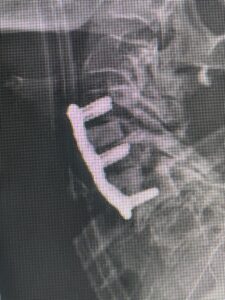

In addition, she had previously undergone both front and back surgery for severe cervical stenosis where her posterior hardware had failed because of her severe osteoporosis requiring us to remove the posterior hardware . This required her to have an anterior or front operation which allowed better fixation to her spine because of the load-sharing nature of the interbody grafts in addition to her anterior cervical plate (Fig 3).

(Fig 3) Lateral Intraoperative Cervical X-ray demonstrating good alignment after C4-C6 anterior cervical discectomy and interbody fusion with plate. Note the interbody grafts help load share the plate in this patient with severe osteoporosis.